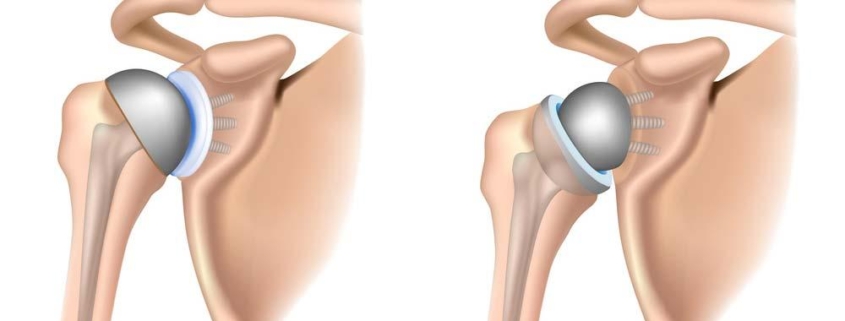

Reverse shoulder arthroplasty, or RSA, is a type of surgery designed to treat a number of shoulder conditions and injuries that cause chronic pain and impair daily functioning. This procedure, also referred to as reverse total shoulder replacement, is often recommended for individuals who have not found adequate relief from non-surgical treatment options.

The term ”reverse” in RSA refers to the fact that artificial components are placed in reverse positions in the shoulder joint, compared to traditional replacements. While there aren’t specific subtypes of RSA, there are varieties of shoulder replacements that differ in design and technique. These can broadly be categorized into:

The goal of a reverse shoulder arthroplasty is to help you get back to doing the things you enjoy without pain and with improved function. During the procedure, the damaged parts of the shoulder are replaced with artificial components.